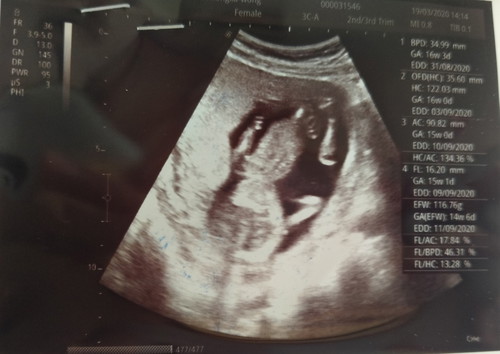

หญิงหรือชายคะ

ตอนอัลตร้าซาวด์กลับตีลังกาให้หมอดูหลายรอบแต่ไม่ให้เห็นสักทีว่าหญิงหรือชาย

รอซาวน์รอบถัดไปค่ะแม่😆